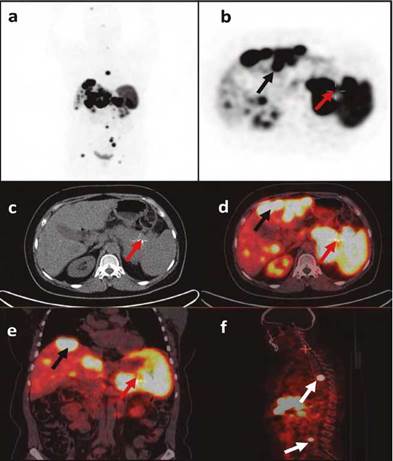

Paciente de 55 años con cuadro de dos años de evolución consistente en dolor en epigastrio e hipocondrio izquierdo y pérdida de peso involuntaria (10 kg), previo al inicio del cuadro con obesidad sin otros antecedentes de importancia. Tomografía de abdomen con reporte de masa (95 x 45 mm) en cuerpo y cola de páncreas (fig. 1a) y múltiples lesiones focales diseminadas en parénquima hepático (fig. 1b). Fue llevada a biopsia hepática y se reportó un tumor neuroendocrino con inmunohistoquímica positiva para cromogranina, sinaptofisina, focalmente para CK20 y negativa para CK7, TTF1 y CDX2, el índice de proliferación Ki-67 fue del 10% (grado 2 por WHO) y no se observaron mitosis en 10 campos de alto poder (CAP). En la tomografía por emisión de positrones (PET) con Galio 68-DOTATOC (fig. 2) se evidenció una masa en cuerpo y cola de páncreas con elevada sobreexpresión de receptores de somatostatina (Krenning 4/4), y múltiples focos hipercaptantes en los ganglios paraaórticos, el hígado, el peritoneo y en la columna vertebral (T6, L4, L5, S1); en PET-FDG (fig. 3) se observó igualmente compromiso hipermetabólico en páncreas y focos metastásicos descritos. Se consideró no candidata a intervención quirúrgica por la extensión de las lesiones hepáticas. Se inició con lanreotide 120 mg subcutáneos mensuales y ácido zoledrónico 4 mg intravenosos trimestrales por el compromiso óseo. Teniendo en cuenta que hubo progresión de la enfermedad a nivel hepático al tercer mes del tratamiento, se indicó quimioterapia con capecitabina (1.500 mg/m2) desde el día 1 al 14 y temozolamida (200 mg/m2) desde el día 10 al 14, ciclos cada 28 días.

Figura 2 PET Galio 68 - DOTATOC. Representación PET (a, b), TAC (c) e imágenes fusionadas (d, e, f). Se observa masa en cuerpo y cola páncreas (flechas rojas), metástasis hepáticas (flechas negras), metástasis en columna (flechas blancas).